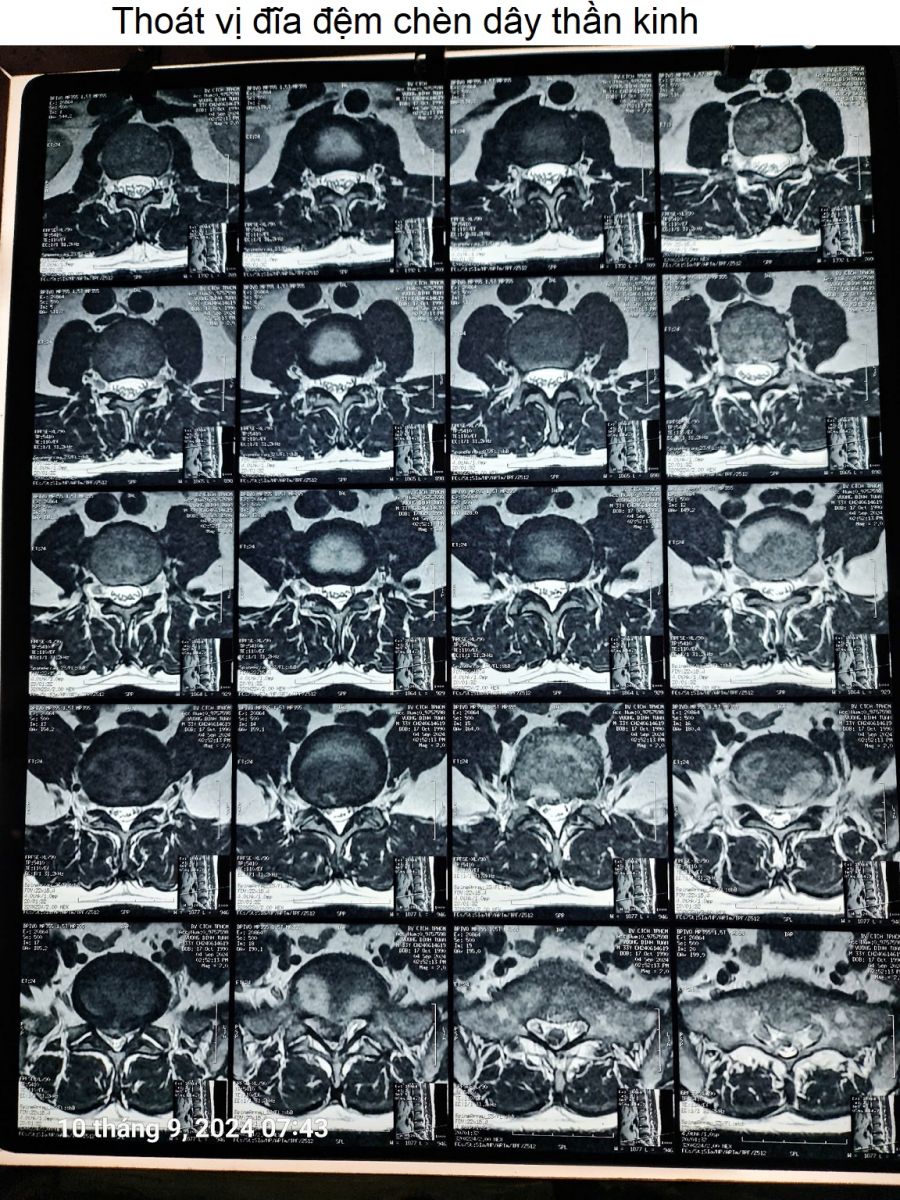

Thoát vị đĩa đệm chèn ép dây thần kinh

Thoát vị đĩa đệm chèn ép dây thần kinh (chèn ép rễ thần kinh). Đây là tình trạng làm cho người bệnh bị đau nhức, tê bì dọc đường đi của dây thần kinh. Nếu chèn ép nặng dễ gây teo cơ, chân yếu hoặc tay yếu, đi lại vận động bị hạn chế.

Hình ảnh thoát vị đĩa đệm chèn ép dây thần kinh, của bác Phùng Quang Thanh ở Nha Trang. Cắt ra từ phim chụp cộng hưởng từ MRI cột sống.

Hình ảnh Thoát vị đĩa đệm L4-L5 chèn dây thần kinh

Chụp cộng hưởng từ MRI phát hiện thoát vị đĩa đệm chèn ép dây (rễ) thần kinh.